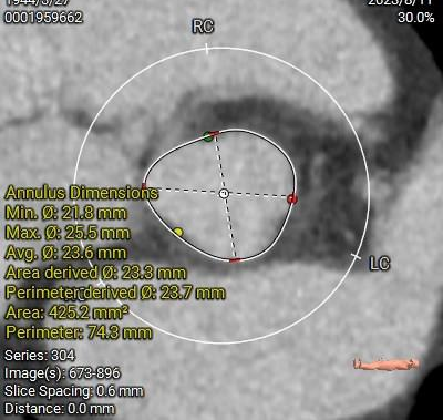

主动脉根部径线:

Annulus23.7mm

LVOT23.6mm

多平面分析:

Sub-223.8mm

Super-223.7mm

Super-425.2mm

Super-624.3mm

Super-825.4mm

Super-1025.4mm